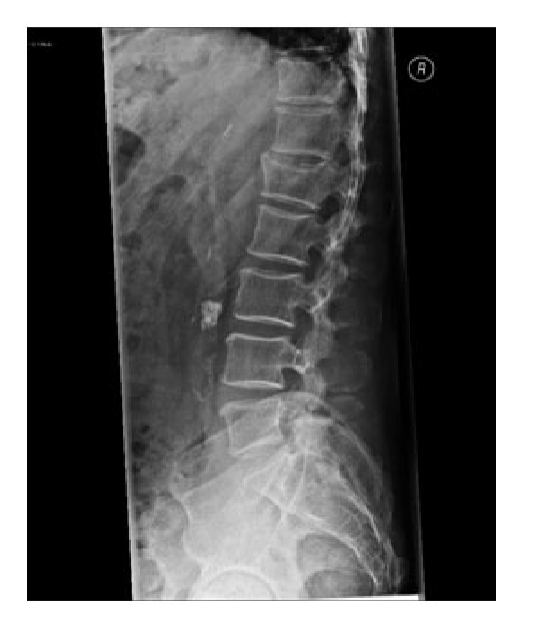

What does this show?

Vertebral compression fracture